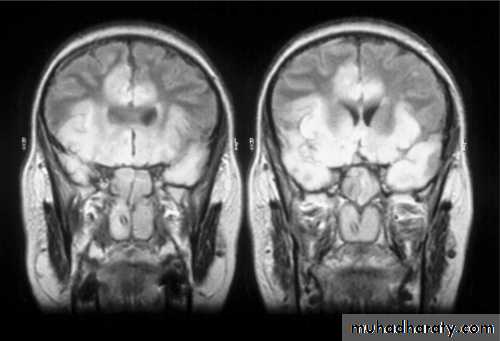

Inflammation can occur in the cortex, white matter, basal ganglia and brain stem, and the distribution of lesions varies with the type of virus.In herpes simplex encephalitis, the temporal lobes are usually primarily affected.

The herpes virus leads to inflammation, infection and necrotizing lesions particularly in the inferior and mesial temporal lobes which may also involve the orbital frontal cortex and limbic structures.

The EEG show periodic sharp-wave complexes from temporal lobe on low amplitude backgroundCT-scan low density lesion within the temporal lobe with mass effect .

MRI-high signal intensity on T2